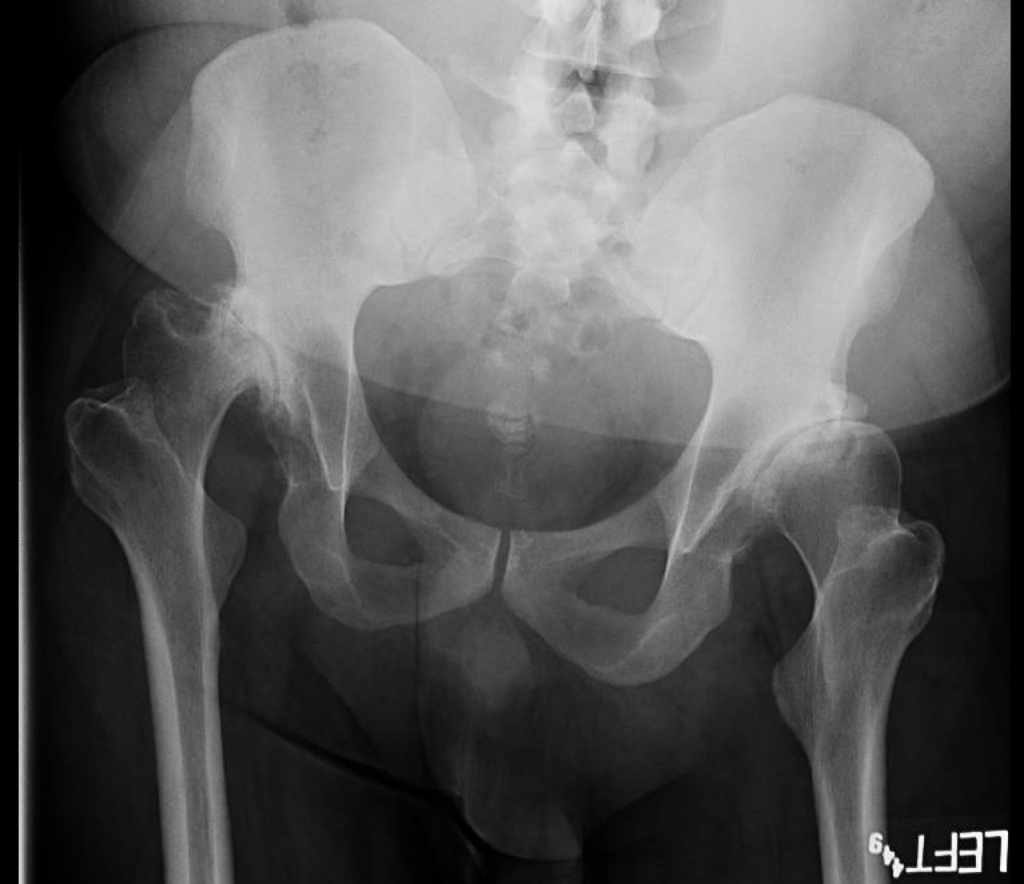

Hip Dysplasia Workup . developmental dysplasia of the hip (ddh) workup: developmental dysplasia of the hip (ddh) describes a spectrum of conditions related to the development of. pediatrics (2019) 143 (1): Pediatricians are often the first to identify developmental dysplasia of the. adult dysplasia of the hip is a disorder of abnormal development of the hip joint resulting in a shallow acetabulum with lack of anterior and. Ultrasonography, plain radiography, ct and mri. developmental dysplasia of the hip (ddh), or in older texts congenital dislocation of the hip (cdh) , denotes aberrant development of the hip. Hip dysplasia treatment depends on the age of the affected person and the extent of the hip damage. developmental dysplasia of the hip (ddh) is a disorder of abnormal development resulting in dysplasia, subluxation, and possible dislocation of.

adult dysplasia of the hip is a disorder of abnormal development of the hip joint resulting in a shallow acetabulum with lack of anterior and. developmental dysplasia of the hip (ddh) is a disorder of abnormal development resulting in dysplasia, subluxation, and possible dislocation of. developmental dysplasia of the hip (ddh) workup: developmental dysplasia of the hip (ddh), or in older texts congenital dislocation of the hip (cdh) , denotes aberrant development of the hip. developmental dysplasia of the hip (ddh) describes a spectrum of conditions related to the development of. Hip dysplasia treatment depends on the age of the affected person and the extent of the hip damage. Ultrasonography, plain radiography, ct and mri. pediatrics (2019) 143 (1): Pediatricians are often the first to identify developmental dysplasia of the.